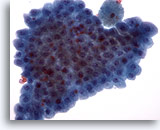

Figure 2

Breast FNA, Benign ductal cells.

Normal breast aspirates yield benign ductal cells, often accompanied by myoepithelial cells. 40x

Figure 2

Breast FNA, Benign ductal cells.

Normal breast aspirates yield benign ductal cells, often accompanied by myoepithelial cells.

40x